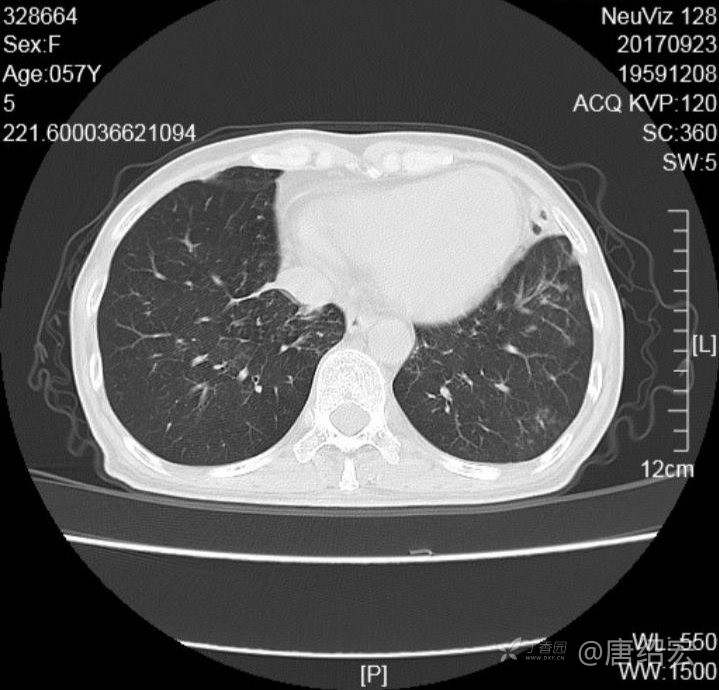

中年女性满肺树芽征还有支气管扩张,考虑什么疾病?

女,57岁,

主诉:发热、咳嗽、咯黄痰,胸闷3天入院。